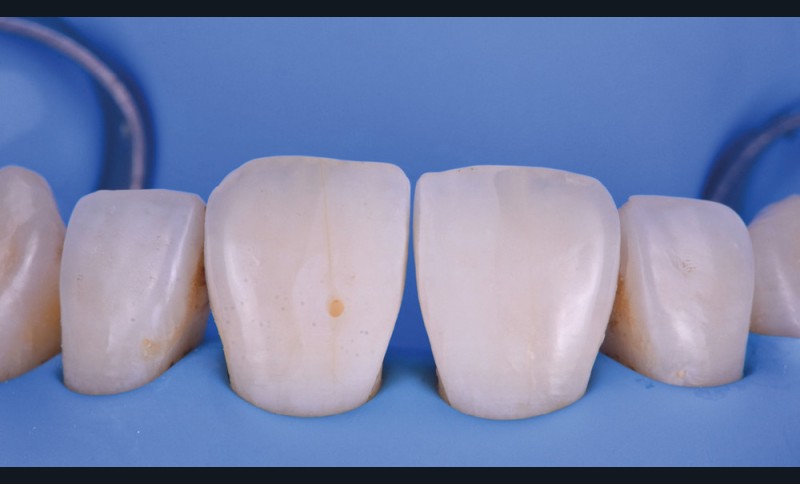

Si les techniques de reconstruction papillaire présentent des résultats non prédictibles, les facettes céramiques peuvent être une réponse fiable au problème des triangles noirs mais imposent une préparation plus marquée. En effet, pour obtenir un profil d’émergence adéquat et une bonne fermeture de l’espace interproximal, il faut préparer les surfaces de contact et venir chercher la ligne de transition palatine, obligeant à retirer une quantité de tissu sain non négligeable.

La fermeture des triangles noirs en technique directe avec des résines composites offre une alternative très favorable avec une approche non invasive, esthétique, un coût réduit et une possibilité de réintervention aisée. Plusieurs méthodes ont été proposées : réalisation à main levée sans matrice (à proscrire), avec bande de matrice transparente plate ou galbée, avec matrice postérieure customisée et utilisée verticalement… Il faut bien comprendre qu’aucun coin en bois ou plastique ne pourra être employé pour stabiliser cette matrice, car il empêcherait la création d’un profil d’émergence anatomique convexe en induisant une déformation concave de la matrice à sa base.